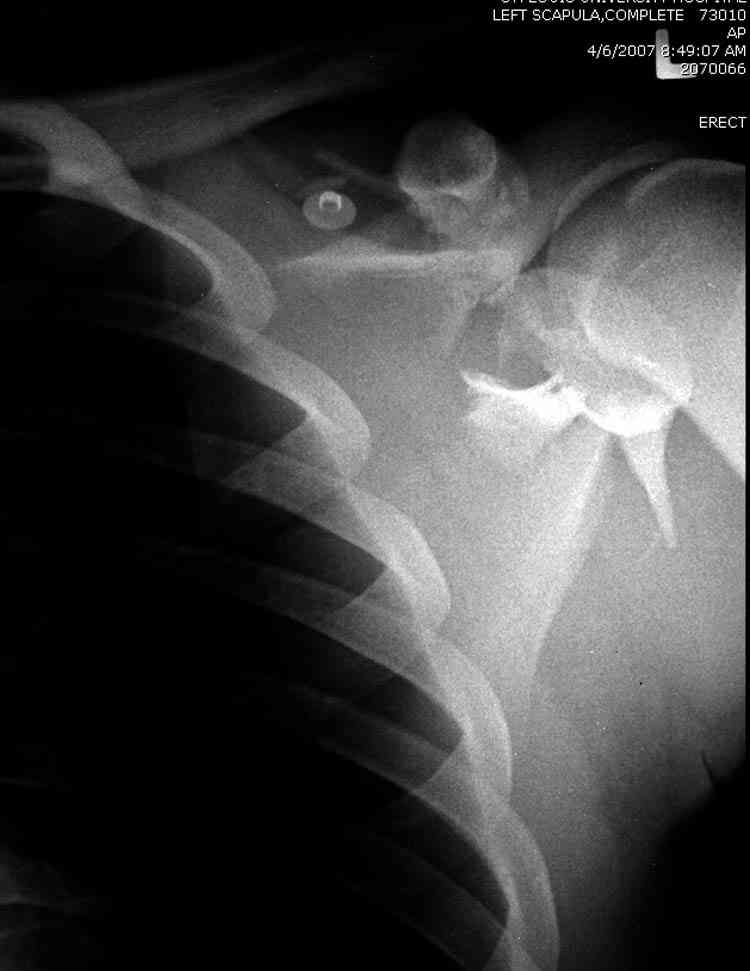

дравствуйте, коллеги. Мужчина 24 лет. Сегодня был прооперирован по Сушко-Илизарову (давно порывался, наконец-то руки дошли :)) На снимке перелом угла лопатки. Довольно крупный размер осколка. Следует ли оперировать такой перелом?Если есть резон оперативного лечения, то каким образом? (рекон. пластина, закрыто пришпилить спицами, винтами). ЭОПа в наличии нет. В области лопатки массивный отек мягких тканей. С уважением, Заднепровский Никита Николаевич

А где там сломанный угол лопатки? Стрелочкой покажите pls?

Для решения насчет оперативного вмещательства на лопатке сперва надо определиться с обьязательными ренгенологическими исследованиями, не менее трех стандартных проекций: прямая, аксиллярная и в позиции виде “Y”.

Прямую снимают под углом в 35 градусов от центра и вид “Y” в 90 градусов к нему. Несмотря на неудобства, больному необходимо сделать

аксиллярный снимок.

К-томографические и Трехмерные(3D)снимки крайне важны для определения внутрисуставных переломов и классификации.

Кроме анатомической классификации, переломы лопатки делятся на стабильные и нестабильные, внутри- и внесуставные и с вовлечением суставной поверхности.

Нестабильные внесуставные переломы лопатки типично сочетаются с переломами ключицы и ребер.

На снимке (№6 компьютерная томограмма и 3D №7) перелом клювовидного отростка.

Посмотрел пациента под рентгеноскопом, определяется изолированный перелом верхнего медиального угла лопатки. Вопрос об операции отпал. Больной машет крылом как пропеллером, пришлось ограничить активность дисциплинирующей "косынкой" ... :))) Отек мягких тканей в области